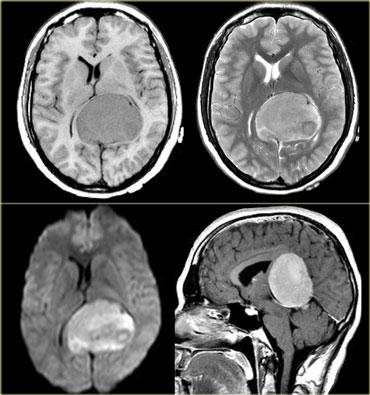

TRÁI: Di căn não. PHẢI: Nhiều u màng não và u thần kinh bao ở bệnh nhân U xơ thần kinh type II (Neurofibromatosis II)

Bệnh đa ổ

Nhiều khối u trong não thường gợi ý bệnh di căn (hình minh họa).

Các u não nguyên phát thường gặp ở một vùng duy nhất, nhưng một số u não như u lympho, u nguyên bào đa hình đa trung tâm (multicentric GBM) và u thần kinh đệm lan tỏa não (gliomatosis cerebri) có thể đa ổ.

Một số khối u có thể đa ổ do di căn gieo rắc: điều này có thể xảy ra trong u nguyên tủy bào (PNET-MB), u màng nội tủy (ependymoma), u nguyên bào đa hình (GBM) và u tế bào ít nhánh (oligodendroglioma).

U màng não và u thần kinh bao có thể xuất hiện nhiều ổ, đặc biệt trong bệnh u xơ thần kinh type II.